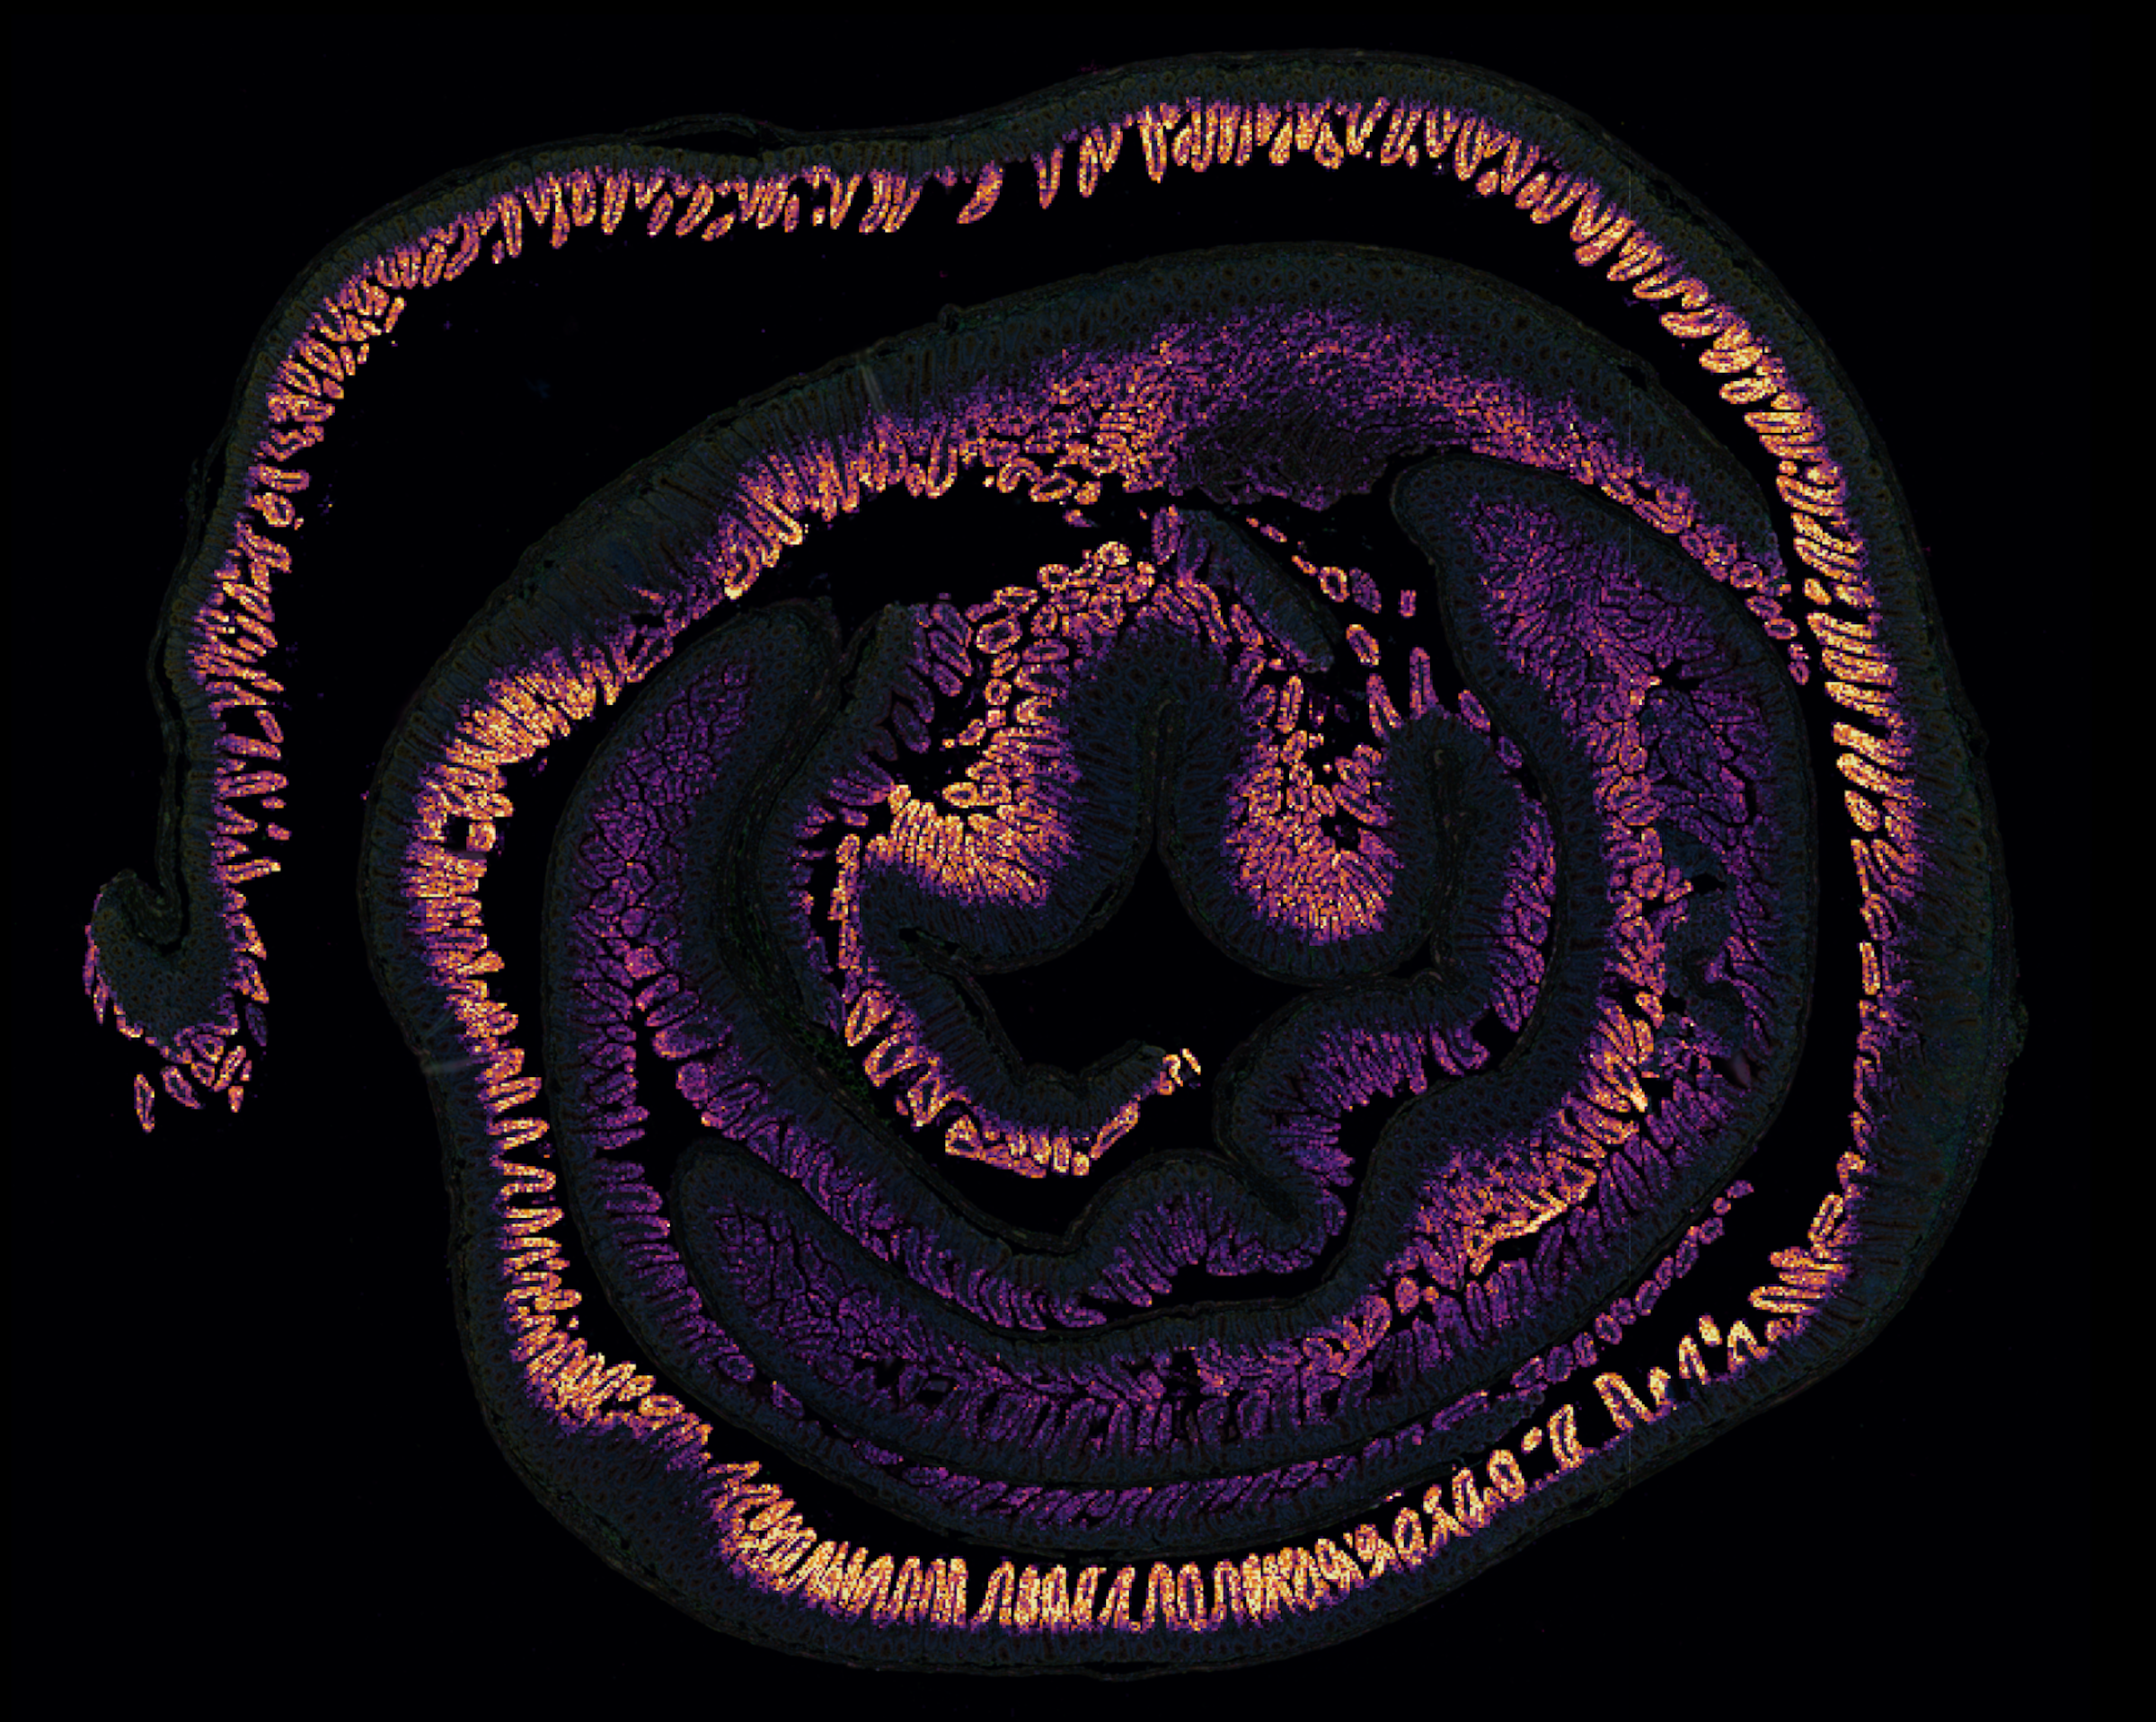

For nearly 20 years I have studied host-microbial interactions, with a primary focus on leveraging genomic and bioinformatic approaches to elucidate mechanisms that regulate inflammation and host defense during infection with zoonotic microbes. During my PhD in Judy Appleton’s lab at Cornell University’s Baker Institute for Animal Health, I studied the immune response during chronic infection with the parasitic helminth, Trichinella spiralis. This work led to the identification of the cytokines IL10 and TGF-β, and eosinophils, as critical regulators of inflammation and immunity to chronic helminth infection. As as postdoc in David Roos’ lab at UPenn, my work shifted from helminth to protozoan parasites, and I began to employ genome-wide transcriptional profiling and genetic screens to identify novel players involved signaling pathways that regulate both immunity and pathogenic inflammation. The results of these studies helped shed light on important immune effector mechanisms, ranging from IL27 signaling in Tregs, to identifying novel enhancers of STAT1 signaling, to reactive oxygen species production by infected monocytes, to TLR3-dependent type I interferon production. In January of 2013, I began a faculty position in the School of Veterinary Medicine at UPenn, were I Co-founded and continue to Co-direct the Center for Host-Microbial Interactions (CHMI). My primary research mission in this role is to develop interdisciplinary ‘One-health’ projects related to microbiology and infectious diseases. In parallel with my research program, I work to engage trainees at the University level in bioinformatics training for managing and analyzing genomic datasets.